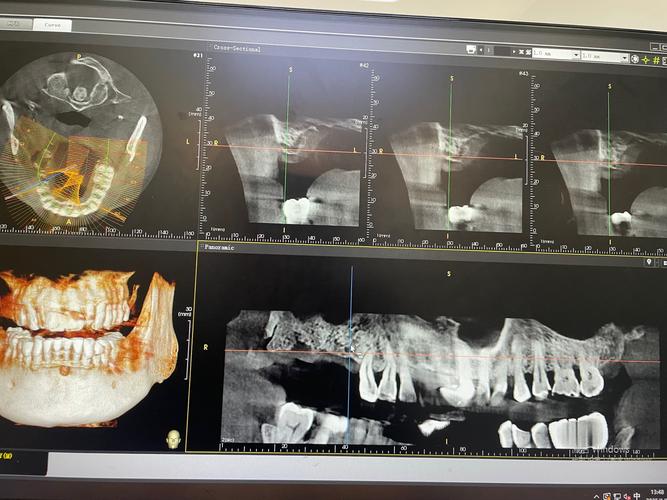

- 数字化种植: 利用CBCT、口扫、数字化导板等技术实现精准种植。

- 初诊检查: 这是至关重要的一步,需要挂她的号(或先挂其他医生号),进行详细的口腔检查、拍CBCT(三维牙片)、取模型、评估全身健康状况等,刘医生会根据检查结果判断你是否适合种植,制定个性化的治疗方案,解释手术过程、风险、费用及预期效果。